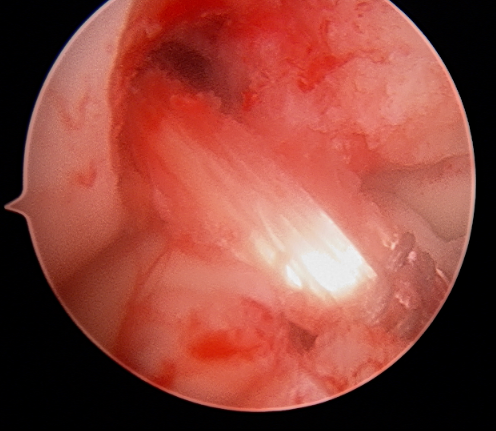

ACL reconstruction surgery is performed arthroscopically using a small camera and small instruments. The surgeon will draw the graft tissue across the knee joint and affix it to the femur (thigh bone) and tibia (shinbone) with a combination of suture, screws or buttons.

This procedure keeps the graft tissue taut and recreates the anatomy and biomechanical function of the ACL. Over time, the patient’s body will turn the reconstructed tendon into a new ligament.